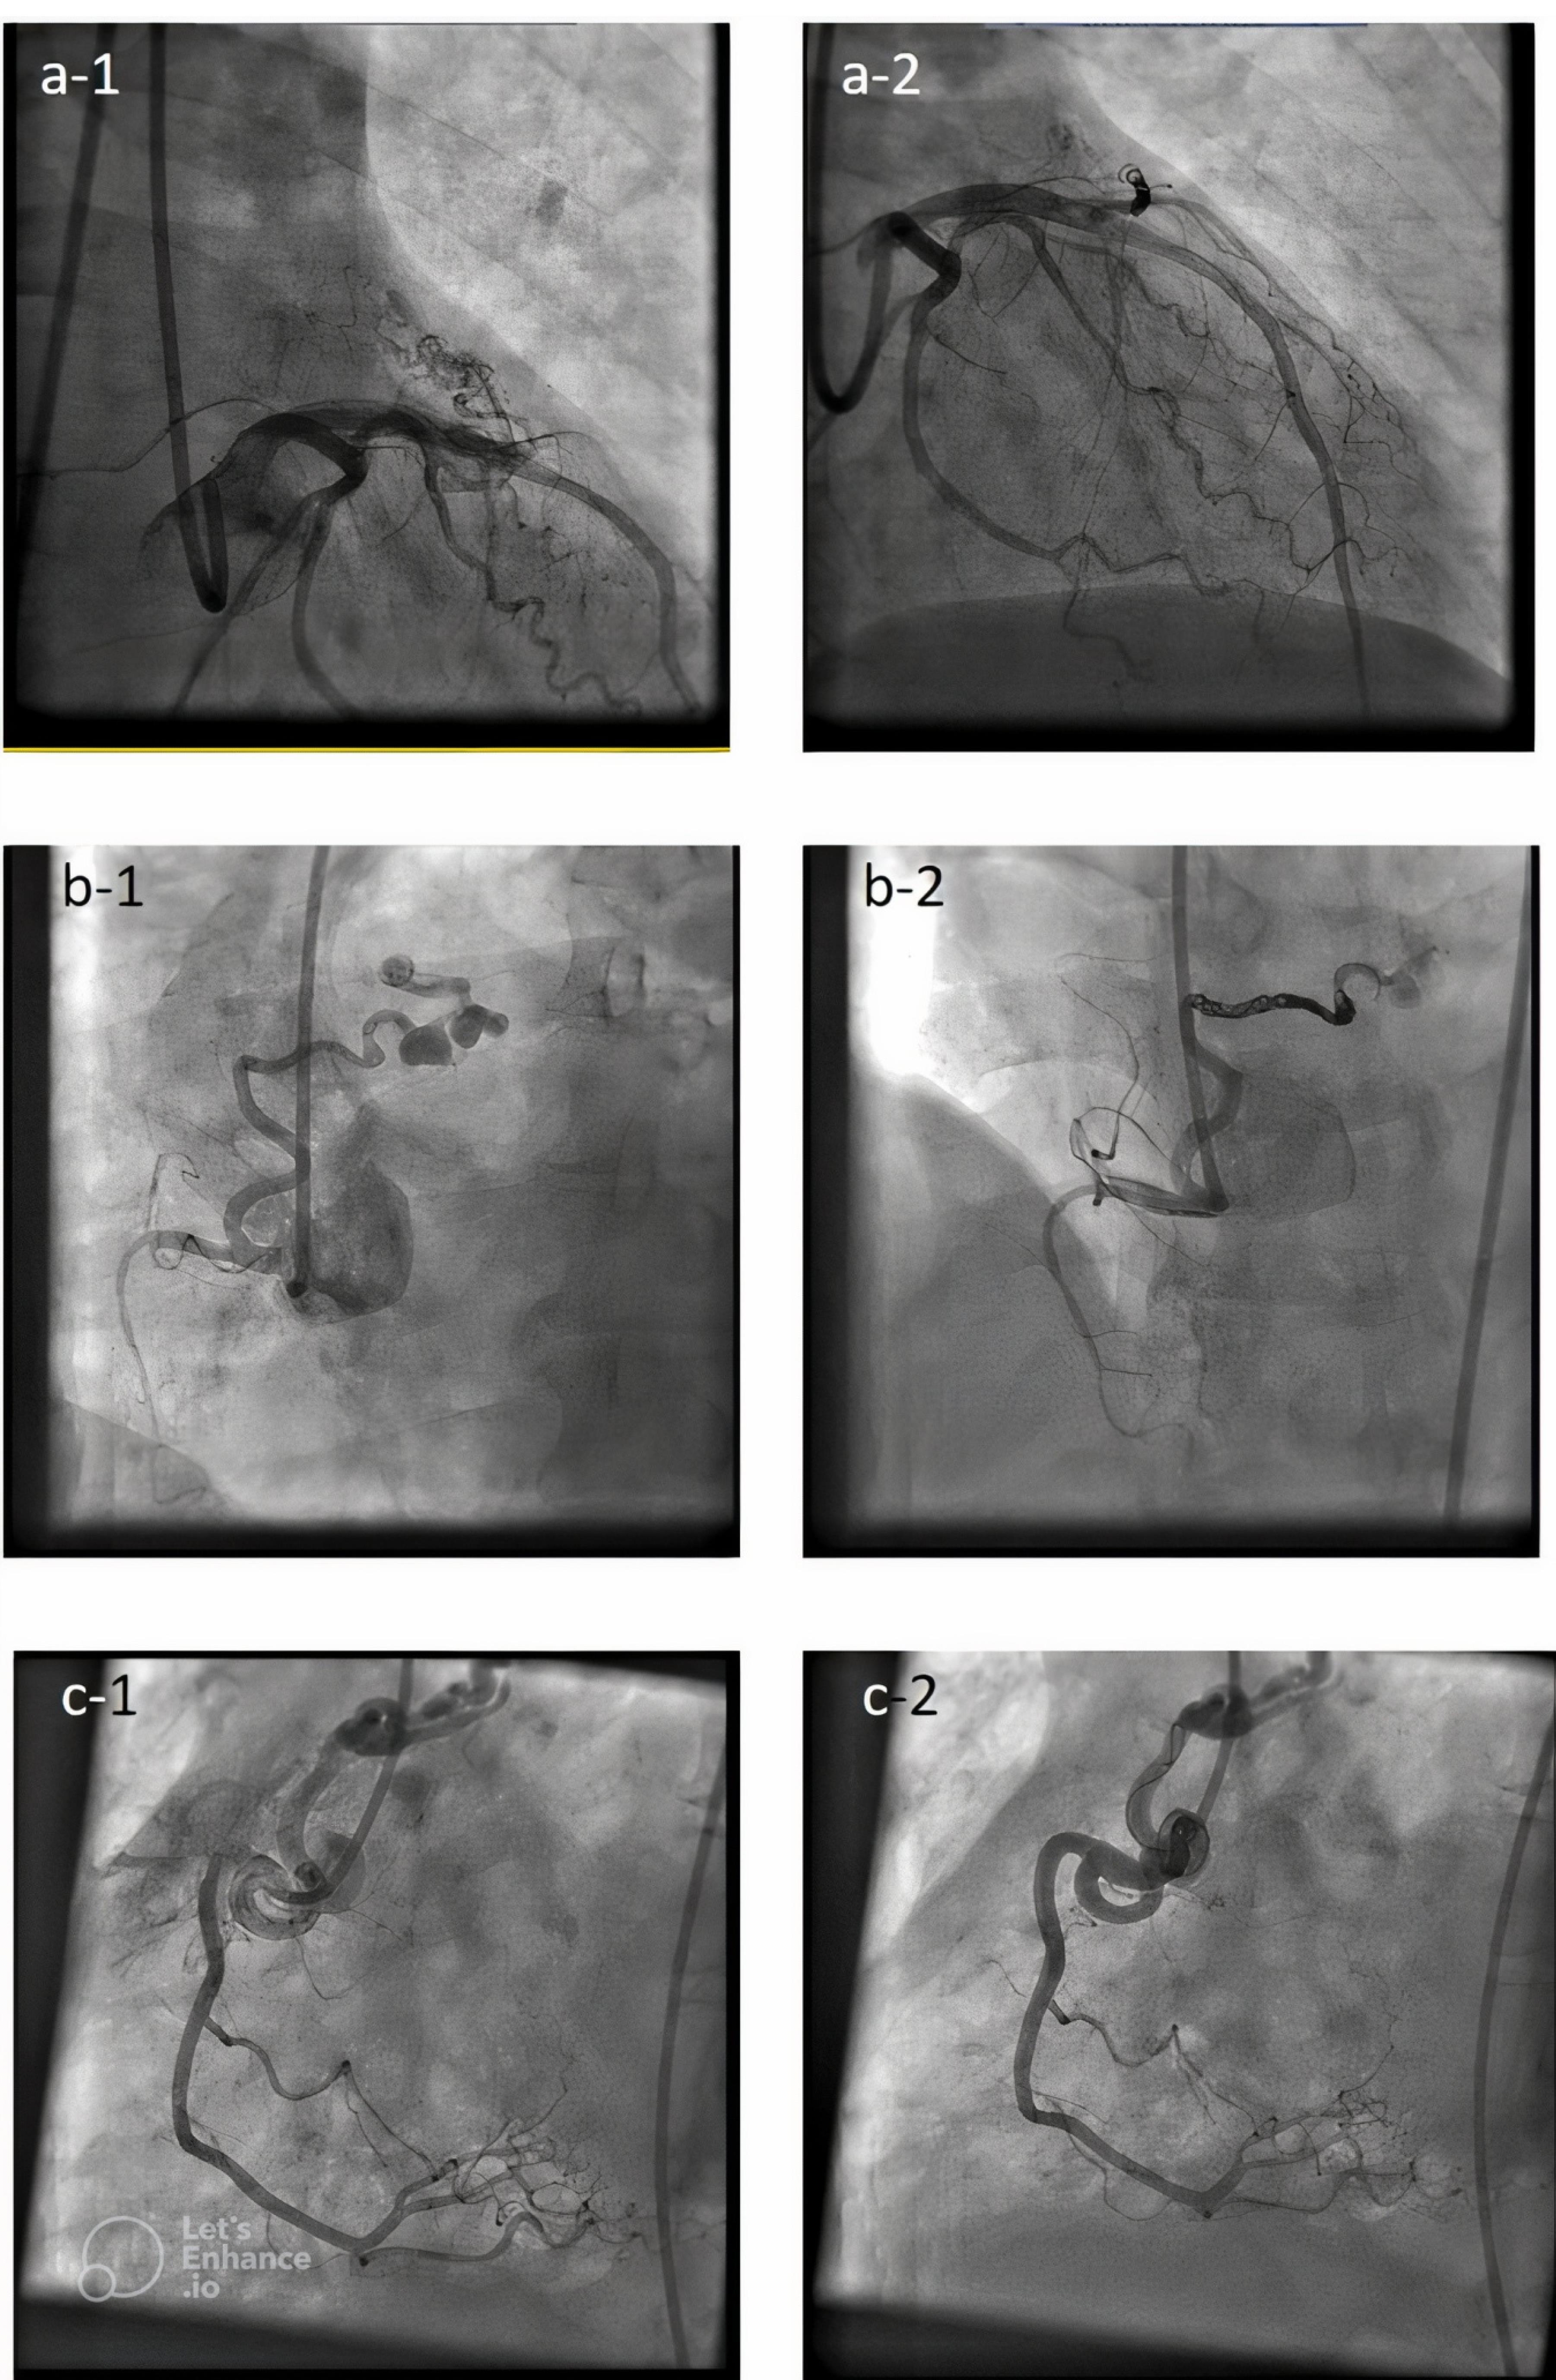

As seen in Figure 1 right coronary artery RCA was the most frequent origin of fistula and most of the fistula drain into the PA. In Figure 2 we showed the frequencies of CAF size based on origin, device type and number of devices that used. In Figure 3, angiographic images of three cases have been showed.

Figure 3.

Angiographic images of 3 cases before and after closing congenital coronary fistulas. (a-1) shows coronary artery fistula originated from LAD (Left anterior descending)and drained into PA (Pulmonary artery) before closure and (a-2) shows fistula in same patient after closure. (b-1) shows coronary artery fistula originated from RCA (Right coronary artery)and drained into PA before closure and (b-2) shows fistula in same patient after closure. (c-1) shows coronary artery fistula originated from RCA And drained into PA before closure and (c-2) shows fistula in same patient after closure